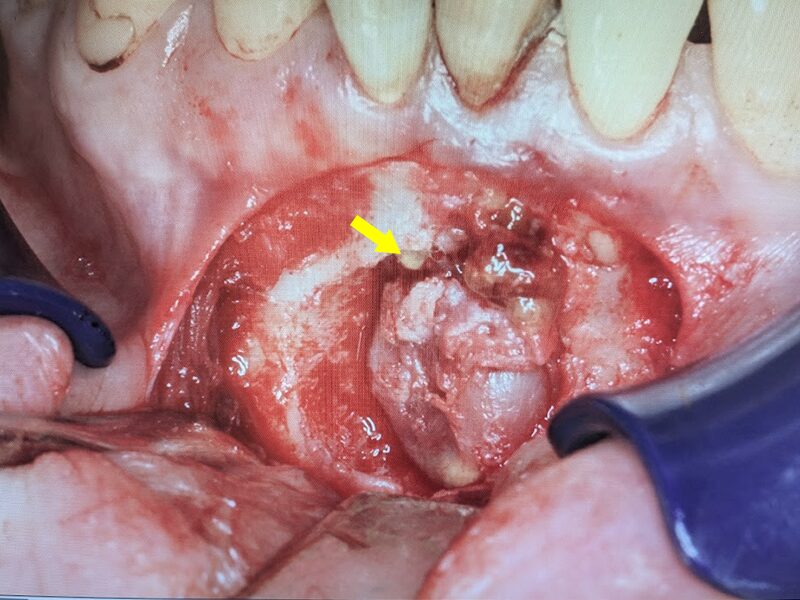

摘出された嚢胞です。

骨再生補填材を入れます。

タブレット状のボナーク(骨再生補填材)で封鎖いたします。